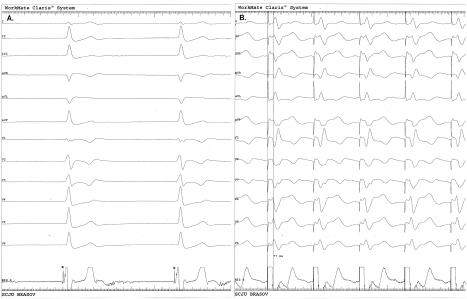

Figure 3

A. A 12-lead ECG and intracardiac electrogram (49mm/s) showed an LBB potential after screwing the lead into the interventricular septum (asterisk). B. Pacing from the lead placed in the LBB area, depicting a typical QR morphology in V1 and an LVAT of 77ms. LBB-left bundle branch; LVAT-left ventricular activation time.

Figure 4

The final 12-lead ECG showed a paced QRS complex with morphology suggestive of the LBB area pacing. ECG - electrocardiogram, LBB - left bundle branch.